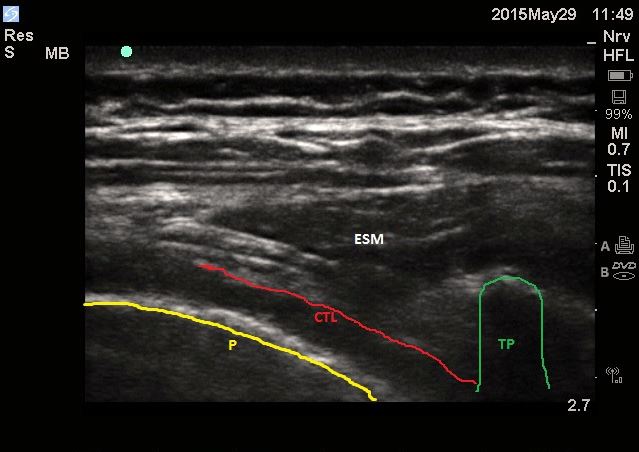

Ultrasound-guided approach: Positioning for ultrasound-guided paravertebral blocks is similar to that used for landmark based approaches. Obtain images of the paravertebral space in the axial/transverse plane with a high-frequency (10–12 MHz) transducer placed lateral to the spinous process. The transverse processes and ribs are seen as hyperechoic structures with acoustic shadowing below them. The paravertebral space can be visualized in this probe orientation as a wedge-shaped hypoechoic layer with the hyperechoic reflections of the pleura below (anterior) and the costotransverse ligamen above (posterior). The hyperechoic line of the pleura can be seen moving with inhalation and exhalation as the visceral and parietal pleura slide against each other. Insert a needle into the paravertebral space and inject local anesthetic, causing a downward or anterior displacement of the pleura. Alternatively, position the ultrasound probe in the sagittal plane. In this orientation, adjacent transverse processes are seen as hyperechoic and squared bony projections. This is in contrast to ribs, which are generally more round in appearance. Deep to the transverse processes, the pleura can generally be easily visualized.